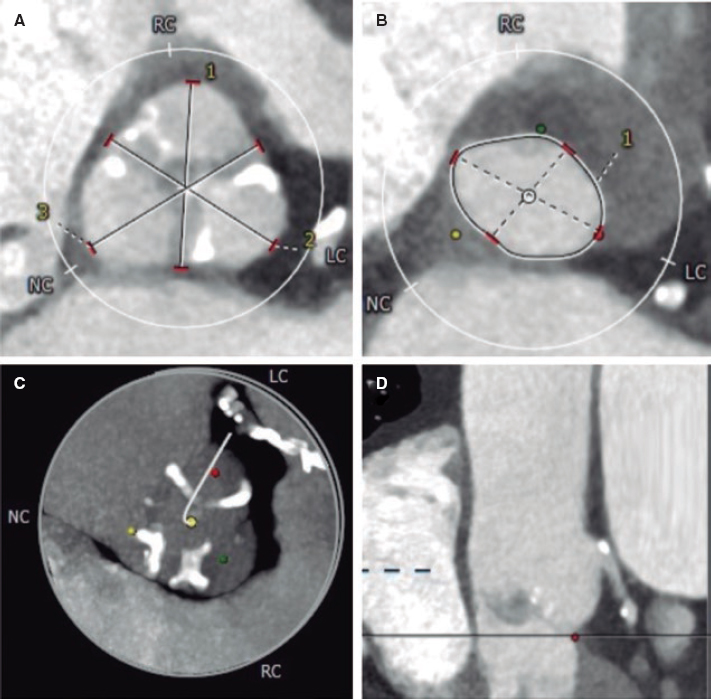

This is the case of a 51-year old male without a past medical history. One month before his admission he experienced fast heart palpitations associated with diaphoresis, nausea and vomit. Both the electrocardiogram and the Holter monitor showed recurring episodes of monomorphic ventricular tachycardia (figure 1). The physical examination confirmed the presence of an aortic ejection murmur exacerbated when performing the Valsalva maneuver. The transthoracic echocardiography showed obstructive asymmetric septal hypertrophy with a 32-mm maximum septal diameter (figure 2A), a 65-mmHg gradient in the left ventricular outflow tract, and systolic anterior motion of the mitral valve with moderate regurgitation. The cardiovascular magnetic resonance imaging confirmed the presence of extensive myocardial fibrosis as a risk factor of sudden death (figure 2B and video 1 of the supplementary data). Amiodarone and propranolol were prescribed, and an automatic defibrillator was implanted as a secondary prevention measure. The patient was readmitted to the hospital 4 months later with signs of electrical storm with multiple discharges provided by the device implanted. Deep sedation, mechanical ventilation, and hemodynamic support were administered, and the stellate ganglion was blocked. However, the patient progression was poor with persistent episodes of ventricular tachycardia that triggered the mapping of cardiac electrophysiology using the CARTO 3 system (Biosense Webster, Israel). The ablation of a septal macroreentrant circuit of the left ventricle associated with the clinical ventricular tachycardia was unsuccessful (figure 2C).

Figure 1. Initial electrocardiogram. Ventricular tachycardia originated at the mid-inferior septum of the left ventricle.

Figure 2. A: transthoracic echocardiography. Interventricular septum with a 32 mm diameter. B: magnetic resonance imaging showing late contrast (arrows). C: mapping of cardiac electrophysiology and ablation attempt of the septal macroreentrant. LO, voltage label; RAM, local electrogram label.